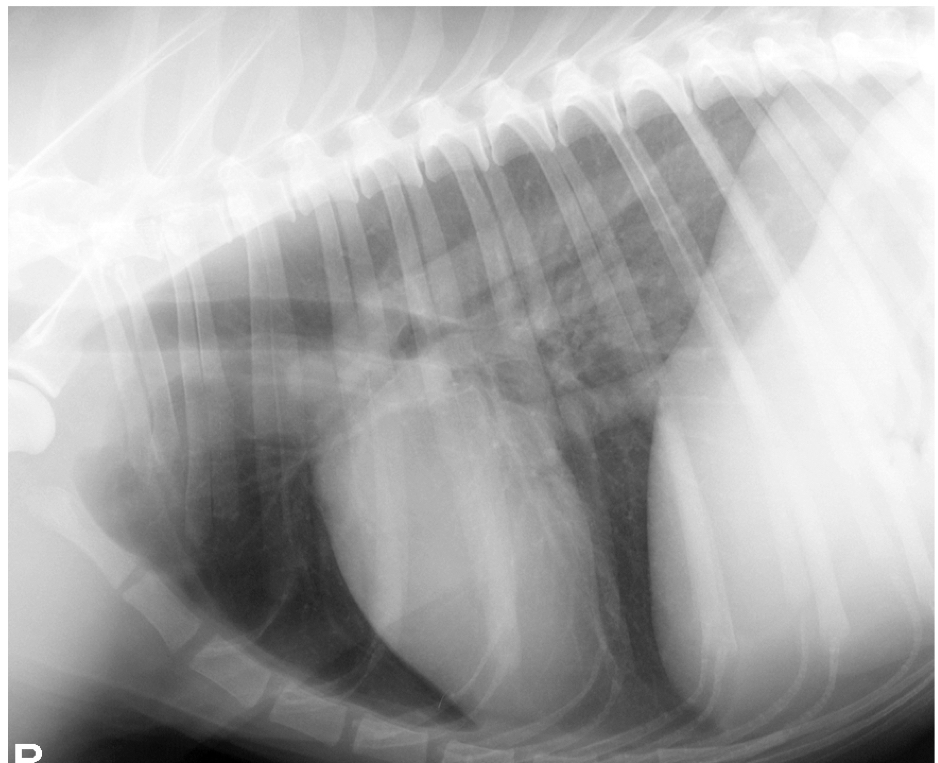

15

Q

what lung pattern and ddx

A

Caudodorsal

Ddx: cardiogenic or non-cardiogenic pulmonary edema